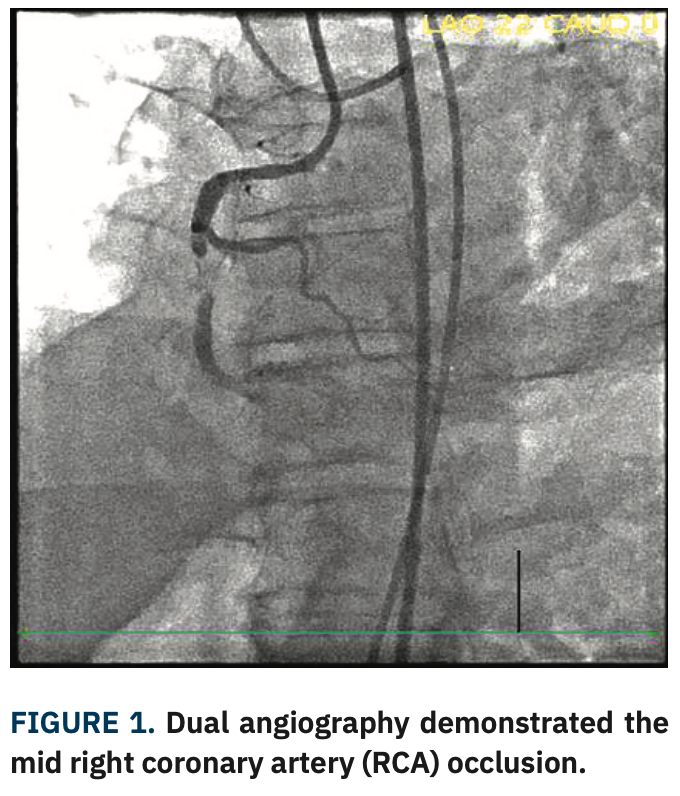

A Corsair Pro microcatheter (Asahi Intecc) was brought antegrade initially with a Gladius Mongo wire (Asahi Intecc); the wire crossed the proximal cap but entered the subintimal space. Both a Pilot 200 (Abbott Vascular) and Hornet 14 wire (Boston Scientific) failed to enter the true lumen distally. A Mongo wire was then advanced with a knuckle fashion to the distal landing zone, followed by the Corsair Pro microcatheter. The Mongo wire was removed and replaced with a Miracle 12 wire (Asahi Intecc), followed by removal of the Corsair Pro and placement of a Stingray balloon (Figure 2). The Miracle 12 wire was removed and a Hornet 14 wire was used to reenter the vessel. Subsequently, the Hornet 14 was removed and swapped for a Pilot 200 wire, which was advanced into the true lumen distally and confirmed on retrograde injection. The Stingray balloon was removed and replaced with a Corsair Pro microcatheter. The Pilot 200 was removed and replaced with a Sion Blue (Asahi Intecc). The Sion Blue was used to wire the distal posterior descending artery (PDA). The Corsair Pro microcatheter was removed. The RCA was pre-dilated with a 3.5 noncompliant balloon, followed by intravascular ultrasound (IVUS). After IVUS, the RCA was stented with 4.0 mm x 38 mm, 4.0 mm x 38 mm, and 4.0 mm x 32 mm Synergy drug-eluting stents (Boston Scientific), all of which were post-dilated with a 5.0 noncompliant balloon. Repeat IVUS showed no edge dissection and good stent apposition. Final angiography showed no residual stenosis (100% to 0%) and TIMI-3 flow distally (Figure 3, Video 2).

ADR-based techniques utilizing the Stingray balloon and guidewires use the subintimal space for crossing the occlusion, followed by reentry into the distal true lumen. This hybrid technique has become the key component of contemporary CTO PCI, especially for crossing more complex occlusions.4 The Stingray balloon is 2.5 mm in diameter, 10 mm in length, and has a flat shape with two side exit ports opposed 180 degrees apart; upon low pressure (4 atmospheres) inflation, it orients with one exit port facing the true lumen and one exit port pointing away from the true lumen. This configuration allows for wire puncture into the distal true lumen when oriented toward the appropriate port. Once the lumen has been punctured, the guidewire can be advanced after a retrograde contrast injection confirms the guidewire is in the true lumen, or exchanged for a stiff-jacketed wire (“stick and swap”). The Stingray balloon is then deflated and exchanged for an over-the-wire catheter to perform subsequent dilatation and stenting of the CTO.4